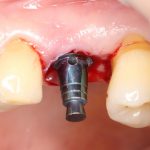

Рекомендации по установке имплантов. Для всех. Часть V.